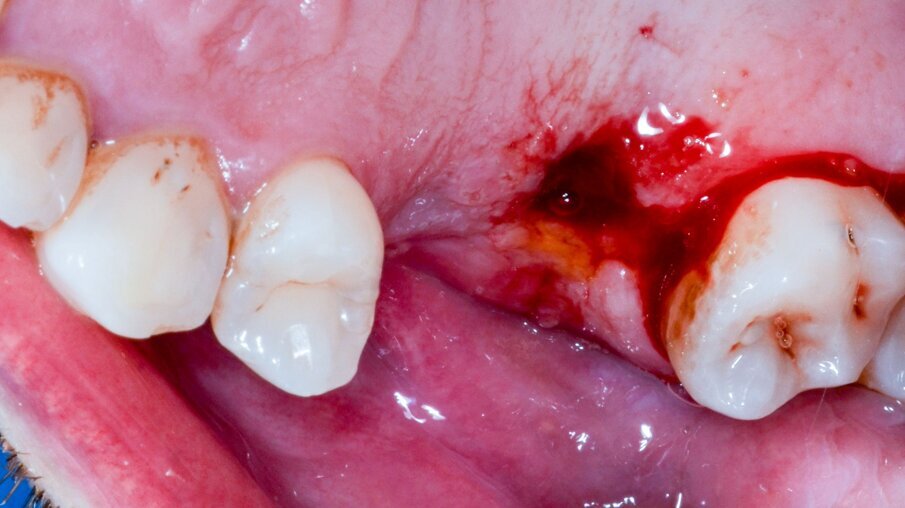

Il paziente R.V. di anni 40 affetto da Neurofibromatosi di tipo I, non fumatore e con neurofibroma palatino è reduce da intervento di avulsione dell’elemento 2.6 e cistectomia con concomitante socket preservation a cielo coperto ed inserimento sempre contestuale di impianto 2.5 in tecnica navigata; necessita per il completamento della riabilitazione dell’emiarcata superiore sinistra dell’inserimento di un secondo impianto in zona 2.6 (Figg. 1a, 1b). La ceratura diagnostica digitale evidenzia, già nel primo intervento, un importante compromesso estetico- igienico accettato dal paziente in virtù della firbomatosi da cui è affetto che ha scoraggiato qualsiasi procedura invasiva (un’esperienza personale nel trattamento del padre riporta un sanguimento difficilmente controllabile della mucosa affetta in corso di chirurgia a cielo aperto ed una guarigione dei tessuti particolarmente imprevedibile anche quando cheratinizzati; nulla è stato trovato al riguardo in letteratura). (Fig. 2).

Figg. 1a, 1b - Situazione iniziale.

Fig. 16 – L’impianto subito dopo il suo posizionamento in chirurgia flapless; approccio preferito in questo caso per l’imprevedibilità della guarigione come già espresso nel testo.